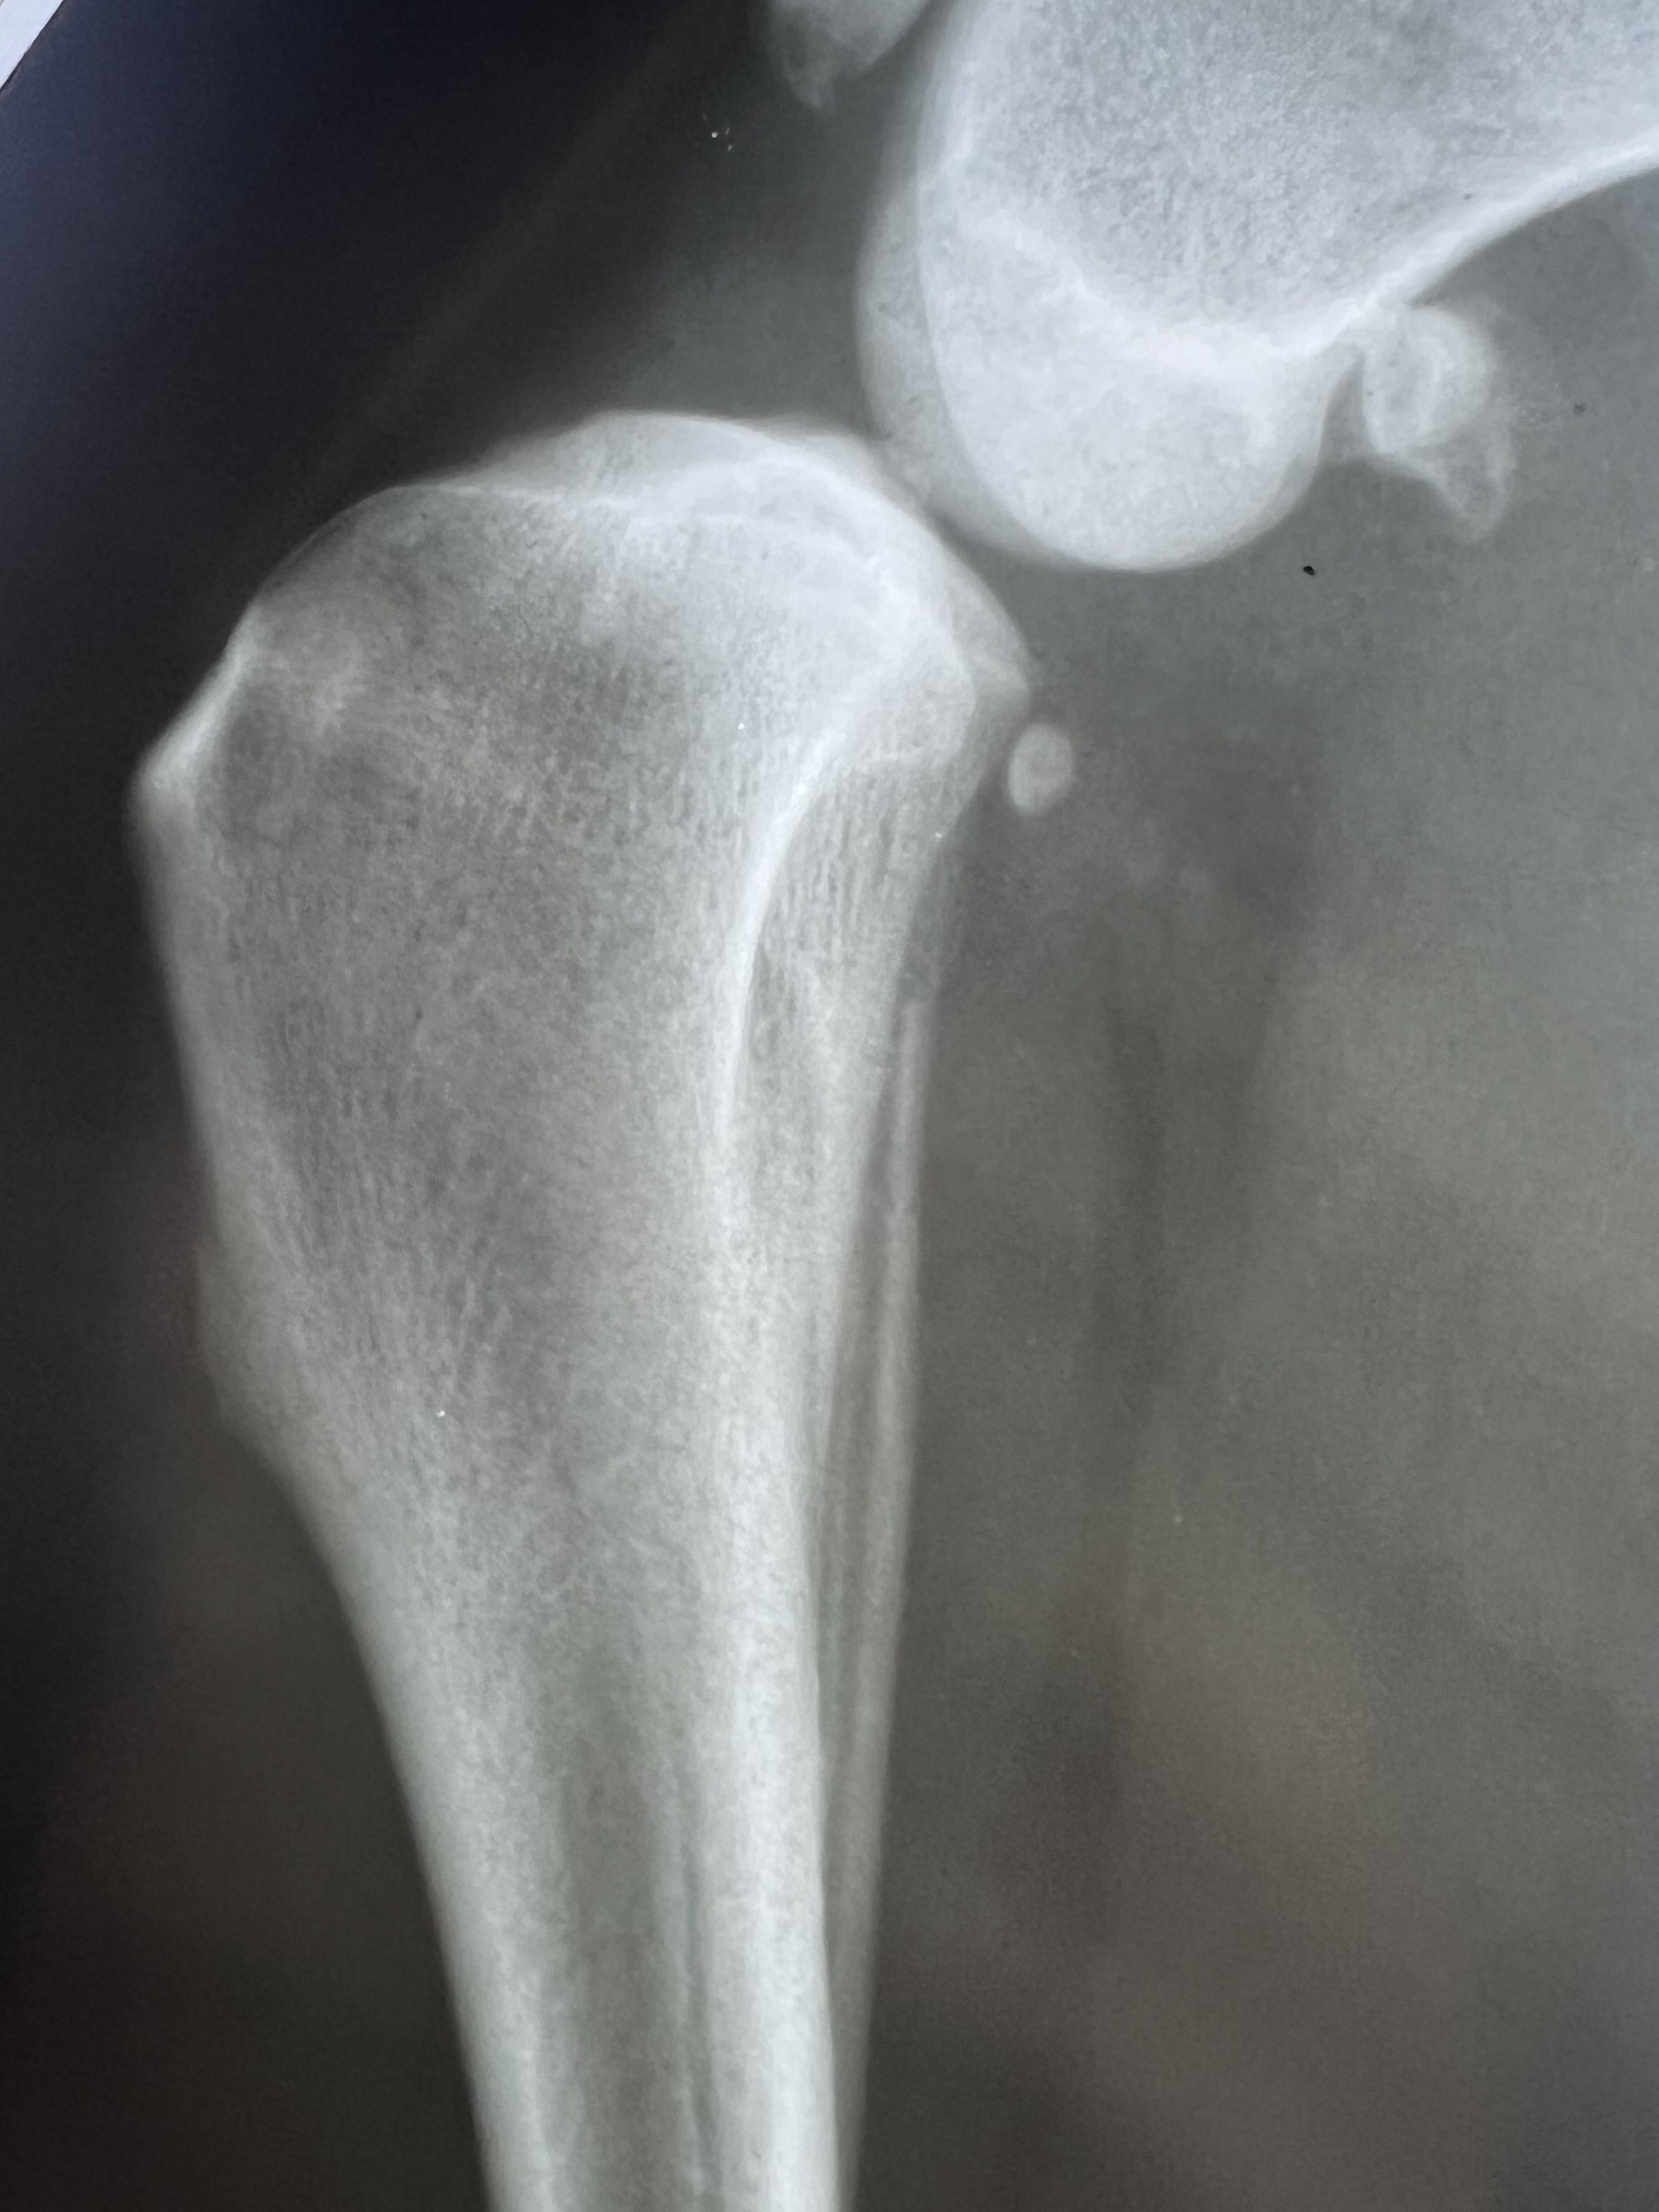

Diagnosis can be made from physical examination alone

but medical history and X-rays help to confirm the suspicion.

On exam, the veterinarian looks for abnormal forward movement of the tibia relative to the femur (known as cranial drawer or tibial thrust), which confirms damage to the ligament.

In partial tears, this motion may not be obvious, but pain on extension of the knee often helps identify the injury.